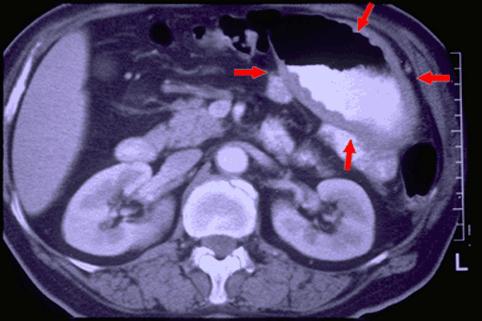

확실한 벽의 비후를 동반한 원발성의 B형 소장 악성 림프종(국립암센터 히가시병원<세키구치 류조>와 큐슈암센터의 공동작성

[Image-ID:938]

질환(병리주체)의 분류

악성 림프계종양/악성 림프종

부위(장기별)

소장/공장

검사방법

CT

종양의 최대경(밀리미터)

40이상

종양의 심달도

s(a)